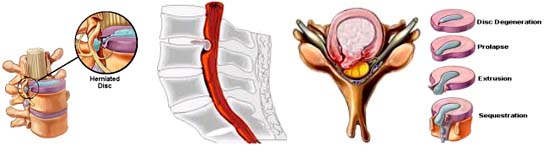

Đĩa đệm là một bộ phận hoặc xem như miếng lót làm giảm sốc cho toàn bộ cột sống, vị trí nằm giữa hai thân đốt sống hay nói rõ hơn, đĩa đệm là chiếc gối đệm đàn hồi có dạng như một thấu kính nằm giữa 2 đốt sống nhằm tạo sự uyển chuyển của cột sống thực hiện các động tác cúi, ưỡn, nghiêng, xoay, ngửa... Đồng thời, đĩa đệm còn có tác dụng như một bộ phận giảm sóc giúp cho cột sống chịu trọng lực từ việc mang vác các vật nặng và chống rung giữ cho cơ thể cân bằng. Để thực hiện được các chức năng trên, đĩa đệm có một cấu tạo rất đặc biệt gồm nhân nhầy ở trong, bao quanh là các vòng sợi xơ và hệ thống các dây chằng. Theo thời gian, đĩa đệm cũng dễ thoái hóa và trở nên giòn, dễ vỡ. Ở những người trẻ thì đĩa đệm mềm dẻo hơn những người già, cũng giống như những cấu trúc khác trong cơ, chúng trở nên mất tính dẻo dai và bền chắc, theo thời gian chúng dễbị tổn thương, thậm chí ở những người trẻ ở độ tuổi 30 cũng có trường hợp bị hư hỏng đĩa đệm khoảng 30%. Khi một đĩa đệm mất tính mềm dẻo, nó có thể bị rách ra và khi đó một khối chất dịch thoát ra ngoài, hiện tượng này gọi là thoát vị đĩa đệm, chất dịch này có thể đè / ép lên rễ thần kinh hoặc tủy gây lên tình trạng đau, tức khi khối thoát vị đó đủ lớn và chèn nặng vào rễ thần kinh. Thoát vị đĩa đệm được giải thích là bình thường đĩa đệm nằm ở khe giữa hai đốt sống, có lớp vỏ sợi bọc nhân nhày ở trung tâm. Nhờ tính đàn hồi, đĩa đệm làm nhiệm vụ như một bộ phận giảm xóc, bảo vệ cột sống khỏi bị chấn thương. Ở những người trên 30 tuổi, đĩa đệm thường không còn mềm mại, nhân nhày có thể bị khô, vòng sụn bên ngoài xơ hóa, rạn nứt và có thể rách. Trên cơ sở đó nếu có một lực tác động mạnh vào cột sống (chấn thương, gắng sức...), nhân nhày có thể qua chỗ rách của đĩa đệm thoát vị ra ngoài chui vào ống sống, chèn ép rễ thần kinh gây đau dọc theo cột sống.

Thoát vị đĩa đệm cột sống luôn là một vấn đề thời sự vì đó là một nguyên nhân phổ biến gâyđau cột sống cổ, cột sống thắt lưng cũng như đau chân tay. Ở Việt Nam có tới 17% người trên 60 tuổi bị mắc chứng đau lưng. Còn ở Mỹ, hằng năm có khoảng 2 triệu người phải nghỉ việc do đau thắt lưng, với chi phí điều trị lên tới 21 tỷ USD. Hiểu biết vấn đề này giúp chúng ta dự phòng có hiệu quả thoát vị đĩa đệm cột sống và giảm bớt chi phí điều trị bệnh. Thuật ngữ về chứng đau khi thoát vị đĩa đệm cột sống cũng khác nhau: nhiều thuật ngữ để mô tả bệnh của đĩa đệm cột sống và các chứng đau liên quan, như thoát vị đĩa đệm (herniated disc), thần kinh bị chèn ép (pinched nerve), lồi đĩa đệm (bulging disc), đau thần kinh tọa (sciatica), lồi đĩa đệm (bulging disc), rách đĩa đệm (ruptured disc), trượt đĩa đệm (slipped disc), lồi đĩa đệm (disc protrusion), thoái hóa đĩa đệm (disc degeneration), đĩa đệm đen (black disc),...hoặc một số thuật ngữ y khoa khác như ruptured spinal disk, herniated bulging disc, bulging disc therapy, bulging disc spinal cord, bulging disc spine, herniated disc surgery, herniated disc mri,... và tất cả được sử dụng chưa thống nhất theo các nhà lâm sàng và nhân viên y tế khác nhau. Thay vì tập trung vào các thuật ngữ về giải phẫu học cột sống, sẽ ích lợi hơn khi bệnh nhân quan tâm tìm hiểu chẩn đoán y khoa nhờ đó xác định nguồn gốc cơn đau tại vị trí cột sống cổ, thắt lưng, ngực như thế nào sẽ tốt hơn. [các thuật ngữ trên sẽ được làm rõ thông qua hình ảnh bên trên]